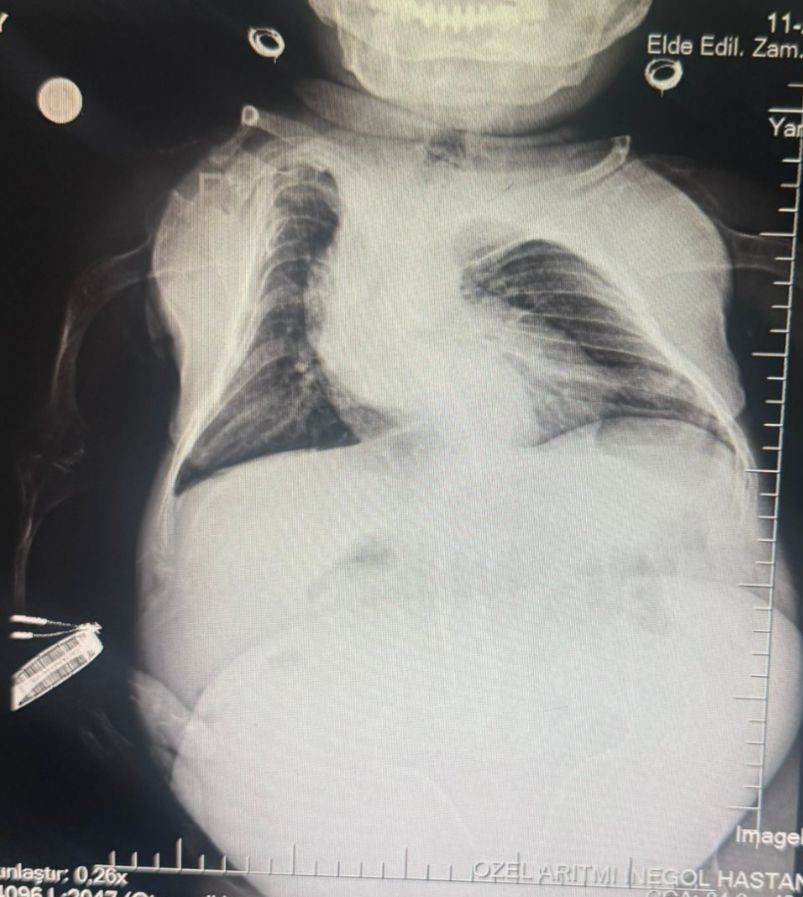

Anestezi Doktoru Mahmut Gül, “Hastamız 30 yaşında. 80 santimetre boyunda, 24 kilo ağırlığında bir kardeşimiz. Kendisinin yumurtalıklarında kist olduğu için ameliyat olması gerekti. Biz bu ameliyatta hastamıza önce büyük bir damar yolu açtık kasıktan. Çünkü damar yolunun çok önemi var ve daha sonrasında ameliyat sırasında belinden uyuşturduk ve ameliyatı sorunsuz bir şekilde belden uyuşturmayla hastamız uyanık bir şekilde tamamladık. Hastadan 3 kilo kist çıktı. Öncesinde 24 kilo olan hastamız, ameliyat sonrasında 21 kiloyla şifalı bir şekilde serviste yatıyor. Ameliyatı bugün oldu. Şu anda da serviste hastamız. Bu tür ameliyatlarda uyutmak hastamız açısından oldukça risklidir. Biz o yüzden bölgesel anesteziyi yani belden uyuşturmayı tercih ettik. Literatürde çok olmayan bir hasta ve güvenli bir şekilde hastanemizde bu ameliyat tamamlandı” dedi.

Kadın Hastalıkları Uzmanı Mustafa Kır, “Hastamızda 20 santimlik tümör vardı kistlik yapıda. Onu başarılı bir operasyonla çıkarttık” şeklinde konuştu.